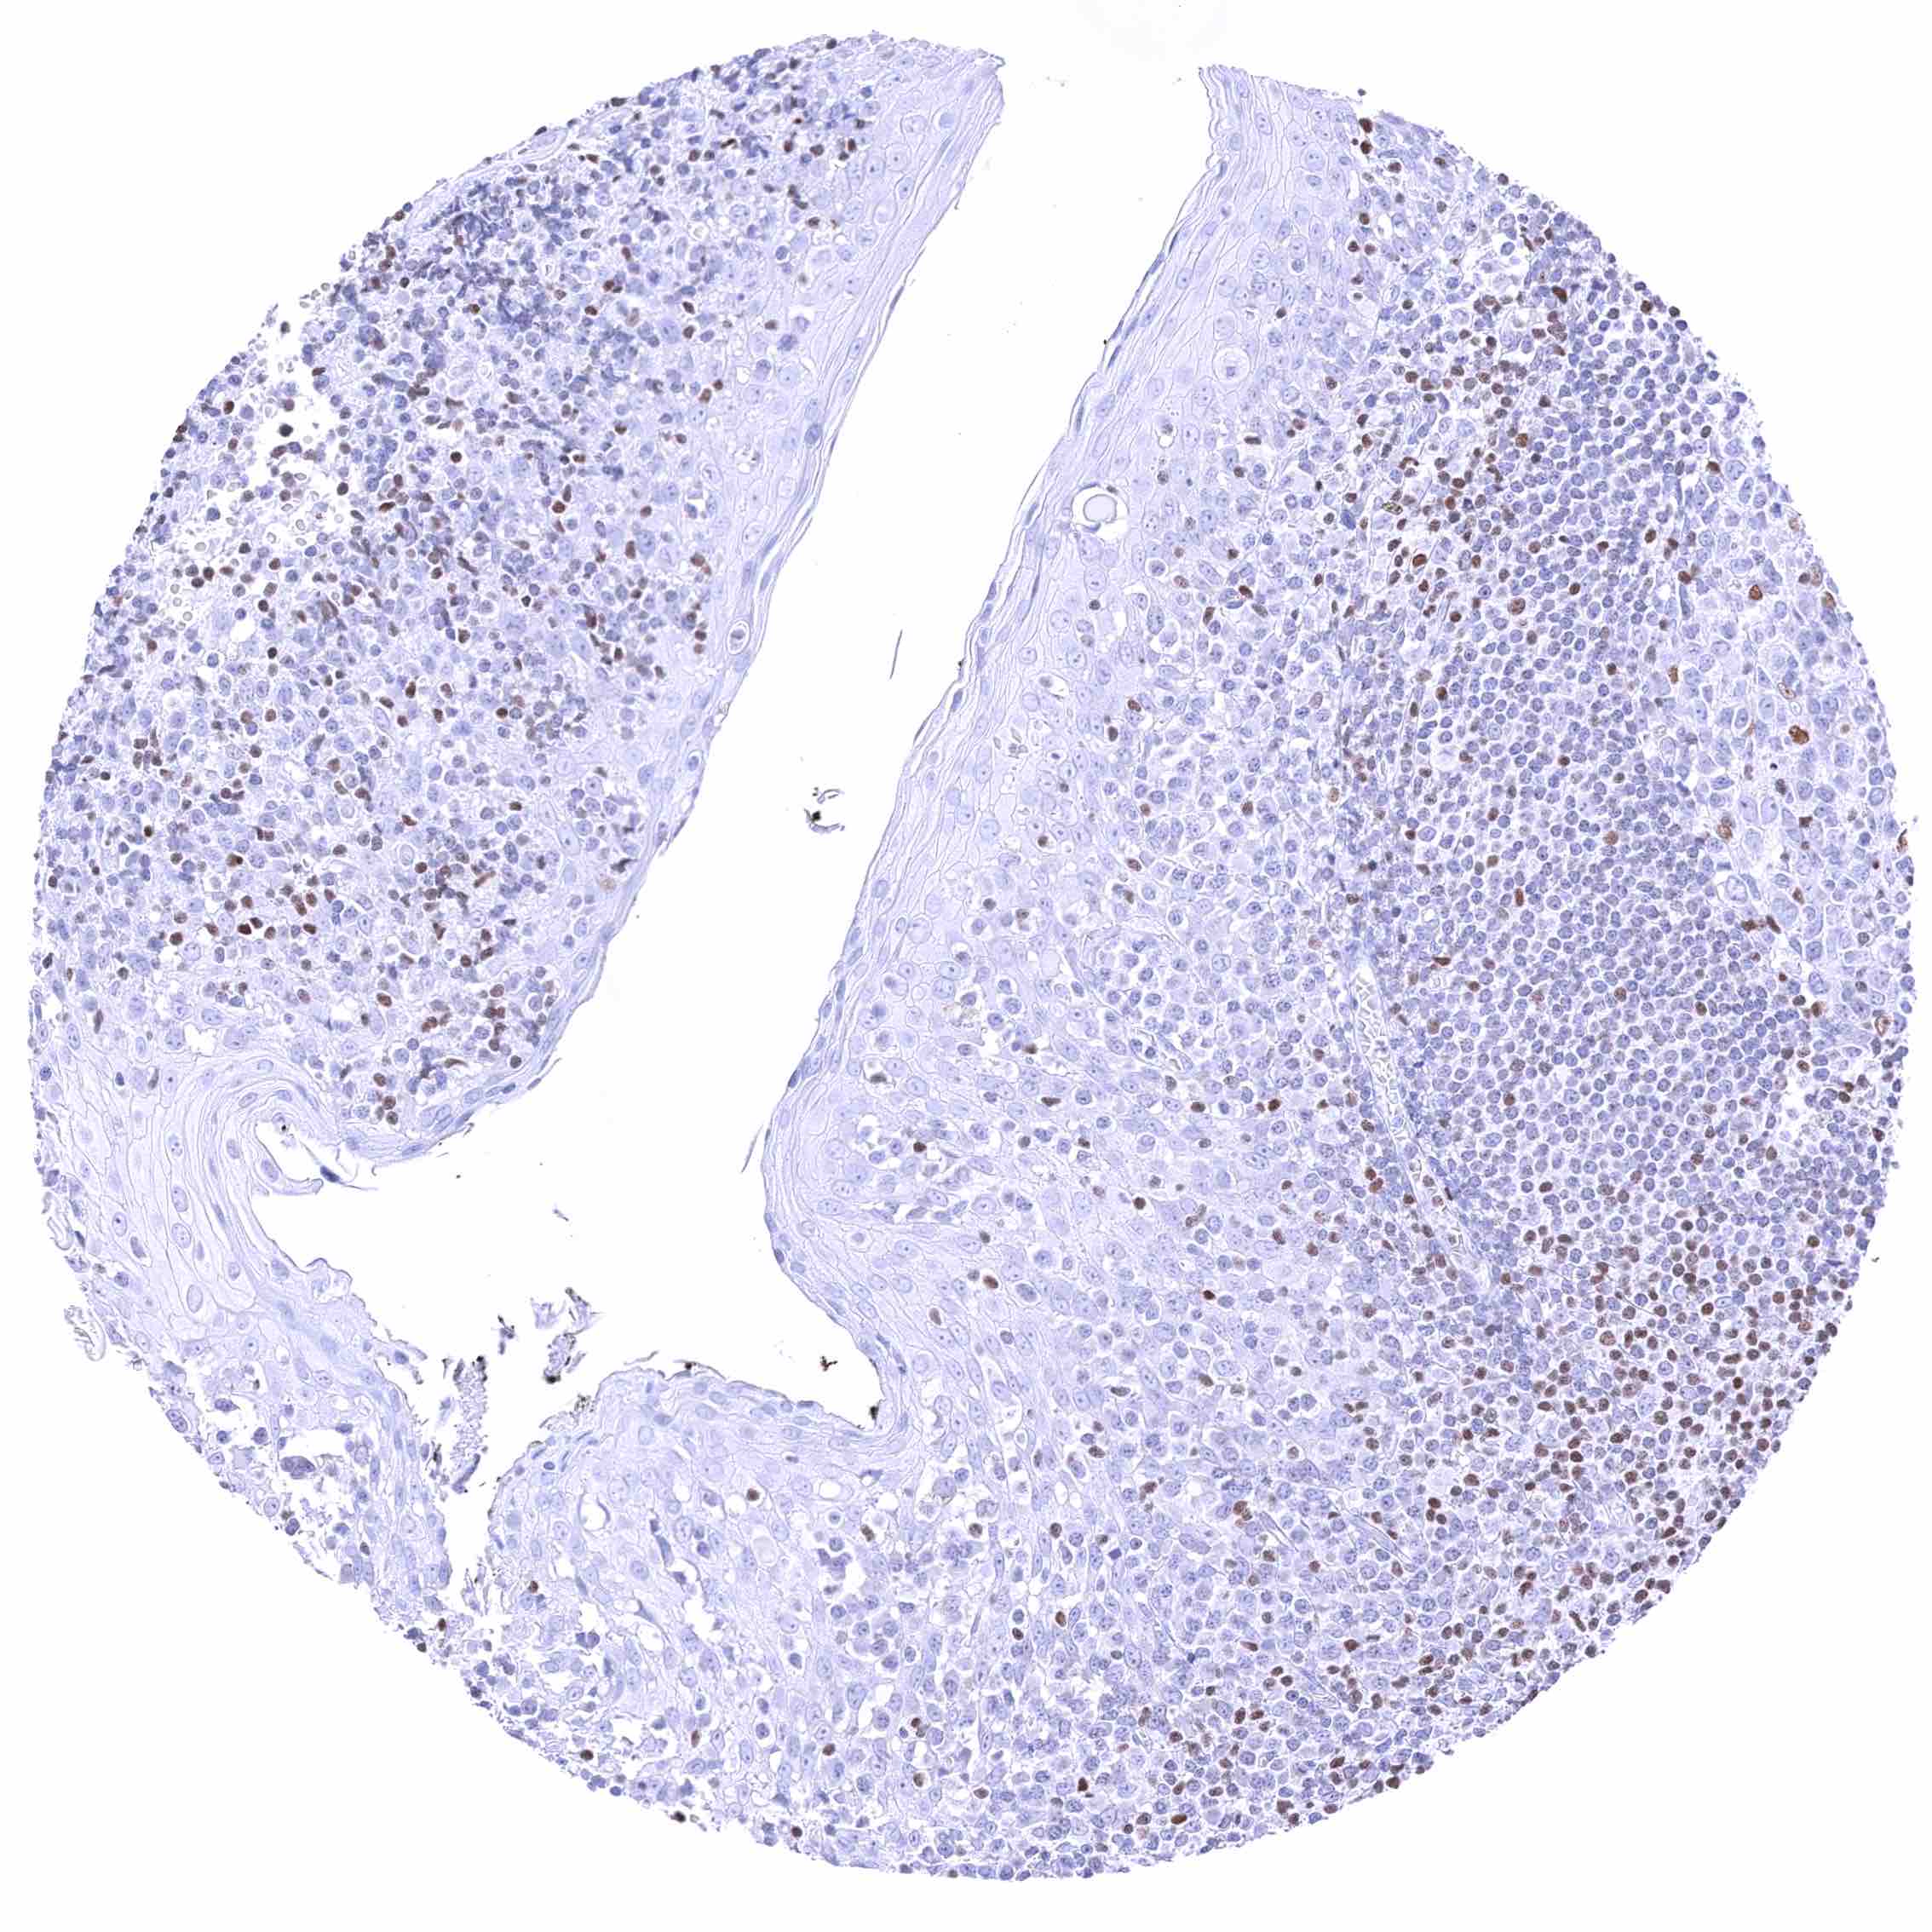

Tonsil – Nuclear GATA3 positivity of a significant fraction of lymphocytes.

Tonsil – Nuclear GATA3 positivity of numerous lymphocytes.

Tonsil, surface epithelium – Nuclear GATA3 positivity of few lymphocytes.